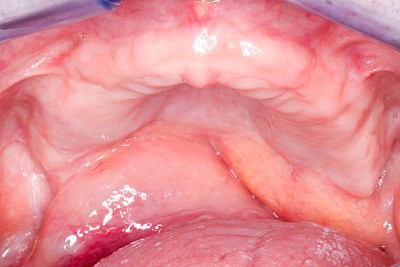

Schwellung ohne Eiter: faltenförmig

Als Sonderform des Reizfibroms können bei Zahnprothesen in den Randbereichen selten am Gaumen, häufiger außen in den Umschlagfalten in Ober- und Unterkiefer auch lappenartige Auffaltungen (Lappenfibrome) beobachtet werden, die ebenfalls aufgrund eines mechanischen Dauerreizes entstehen. Alle diese Veränderungen sind in der Regel eher wenig schmerzhaft – auch wenn man darauf drückt. Hier sollte zeitnah mit einem Zahnarzt eine Abklärung erfolgen.